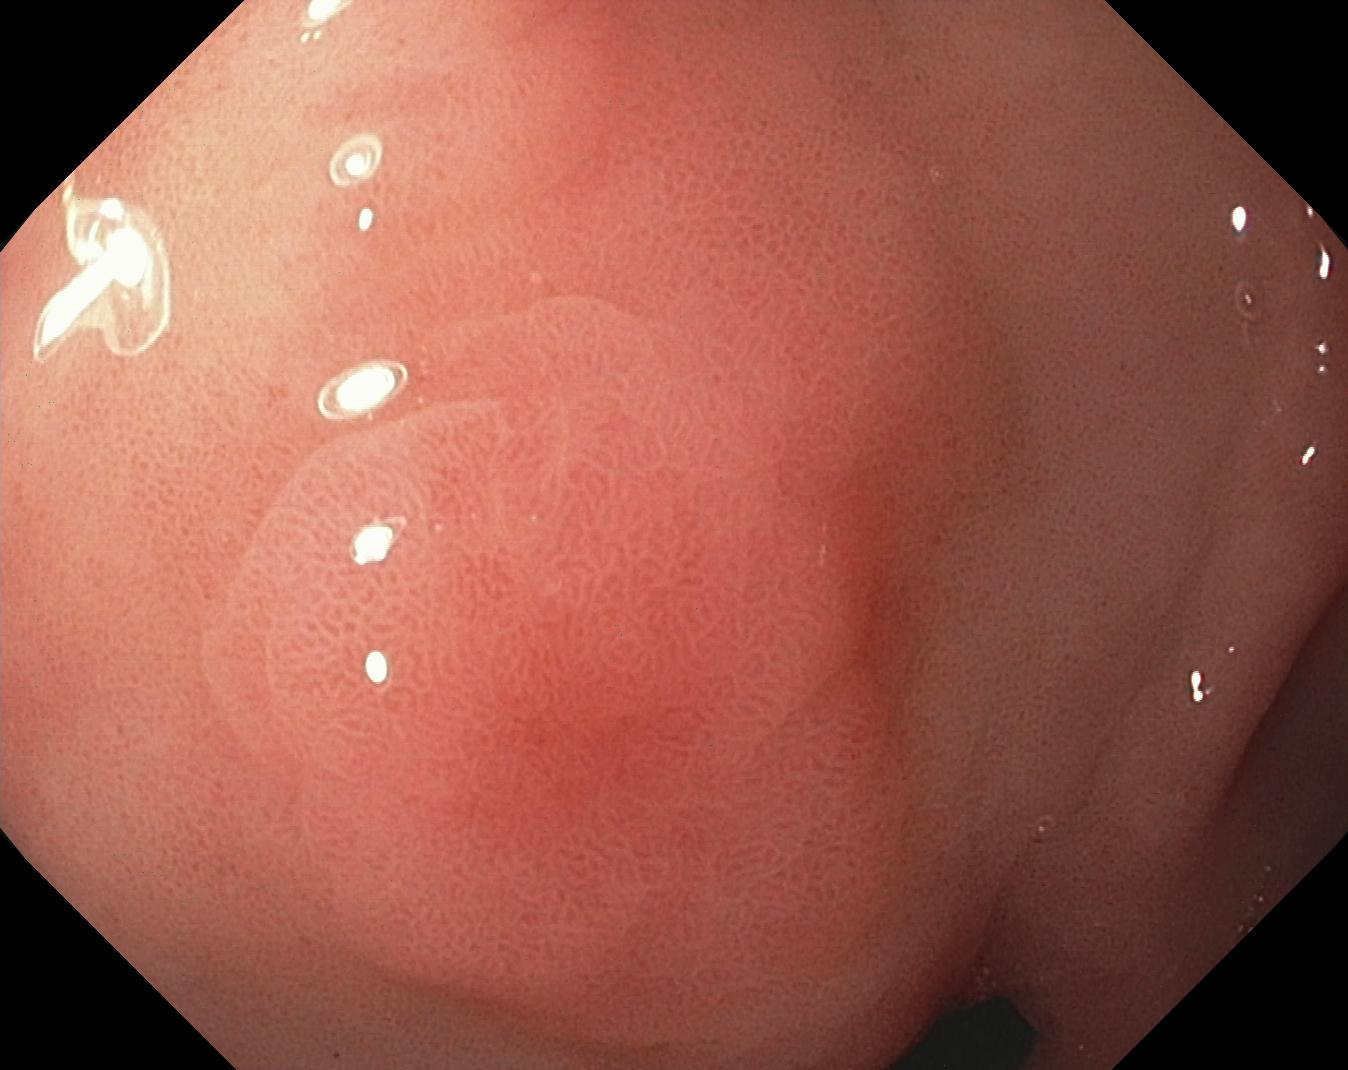

We have used a polyp dataset published with HyperKvasir dataset [51], which consists of polyp findings extracted from endoscopy examinations. HyperKvasir contains polyp images with corresponding segmentation masks annotated by medical experts. We use only this polyp dataset as a case study because of the time and resource-consuming training process of the SinGAN-Seg pipeline. However, the SinGAN-Seg model and pipeline can be used for any segmentation dataset.

A few sample images and the corresponding masks of the polyp dataset in HyperKvasir are shown in Fig 2. The polyp images are RGB images. The masks of the polyp images are single-channel images with white () for true pixels, which represent polyp regions, and black () for false pixels, which represent clean colon or background regions. In this dataset, there are different sizes of polyps. The distribution of polyp sizes as a percentage of the full image size is presented in the histogram plot in Fig 3, and we can observe that there are more relatively small polyps compared to larger polyps. Additionally, a subset of this dataset was used to prove that the performance of segmentation models trained with small datasets can be improved using our SinGAN-Seg pipeline, and the whole dataset was used to show the effect of using SinGAN-Seg generated synthetic images instead of a large dataset which has enough data to train segmentation models. In this regard, this dataset was used for two purposes: